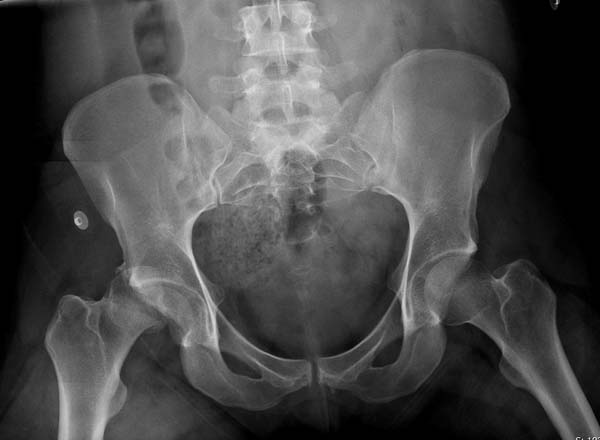

Уважаемые коллеги добрый вечер! Хотелось бы узнать ваше мнение о возможных ранних сроках наступления асептического некроза или коксартроза при данном виде оперативного лечения, может кто-то уже оперировал данную патологию и есть наблюдения. Случай практически идентичный описанный в январе 2015 на ортофоруме Никитой Николаевичем Заднепровским. Молодой человек 20 лет ДТП 23.02.2015, Диагноз: Сочетанная травма. Закрытый переломо-вывих головки и перелом заднего края вертлужной впадины (Pipkin4) правой бедренной кости. Открытый подтаранный вывих правой стопы. При поступлении в ЦРБ вправление вывиха головки бедра и подтаранного вывиха стопы.

Далее перевод к нам в Травмоцентр и 03.03.2015. через 8 дней операция, выполнен остеосинтез головки 3-мя самокомпрессирующими винтами Autofix под разными углами с погружением в субхондральный слой. Доступ Kocher-Langenbeck с флип-остеотомией большого вертела и задним хирургическим вывихом головки бедра. В полости сустава два свободно-лежачих фрагмента хряща головки, которые были удалены. На снимках виден дефект хряща головки после репозиции. Небольшой фрагмент заднего края фиксирован двумя спонгиозными винтами. Далее шов раны с дренированием. На 2 сутки пациент поворачивался на здоровый бок с валиком между ног, на 4 сутки сидел в кровати и на 6 сутки ходил с помощью костылей.

КТ после вправления - это последнее?

На мой взгляд, развитие артроза и AVN в большей степени зависит от давности вывиха и качества оперативной техники. Хирургический вывих бедра- не самая простая процедура и с подводными камнями, в остеосинтезе из переднего доступа тоже есть проблемы.

Здесь значимый задний край с подвывихом бедра кзади и острым краем вертлуги - задний доступ с вывихом и синтезом заднего края винтами и пластиной